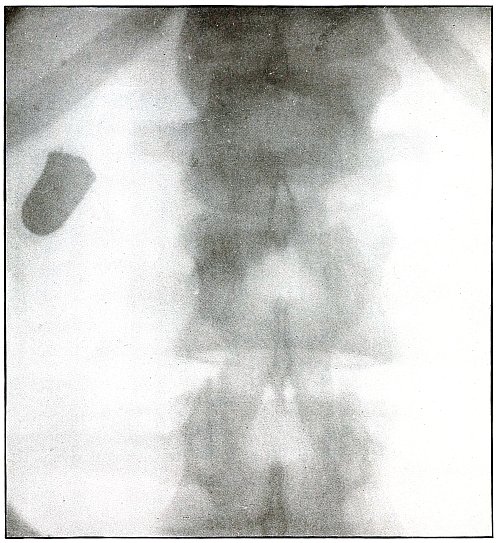

PELVIS.

Plate 46.

[Pg 103]

Rifle—Plate 46.

PELVIS.

Gunshot Wound of the Pelvis,

with Lodgment of the Missile in the Abdomen.

The course of the bullet was from behind forward, striking the crest

of the ilium, on which it was deflected, and spattering off some lead

fragments. The slight penetration indicates a velocity of extremely

long range and a striking energy lessened by ricochet.

The irregular outline of the shadow of the projectile shows its

deformity, and the blurred outline indicates intra-abdominal movement

with respiration.

While the missile, as revealed by its shadow, is not a shrapnel ball,

the distribution of lead particles is more suggestive of a shrapnel

than of a rifle projectile, and the ballistic conditions are more

characteristic of the former than of the latter.

There was no abdominal reaction; the invasion of the abdomen was

revealed by the radiograph.

The treatment in such cases is noninterference unless subsequent

developments furnish definite indications.